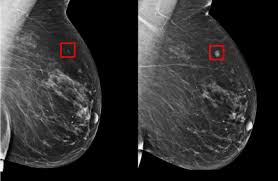

Abdominal Ct Scan Information Mount Sinai New York from ssl.adam.com Detection of breast cancer from a chest ct scan ordered to check for pathology other than breast cancer is commonly referred to as an incidental finding. Too much weight can damage the scanner. A ct scan can show whether breast cancer has spread to the lungs or liver. There is far better contrast enhancement and better tumor detection. In diagnosing inflammatory breast cancer and other breast cancer types and staging the disease metastatic cancer detection. In general breast cancer can be detected on a routine chest ct scan regardless of if contrast media is used or not. This system uses gray transformation for image contrast enhancement. Ct stands for computed tomography.

Imaging In Breast Cancer Magnetic Resonance Imaging Breast Cancer Research Full Text from media.springernature.com Ct scans can detect bone and joint problems, like complex bone fractures and tumors. Ct scans are sometimes referred to as cat scans or computed tomography scans. In contrast with bone scans, which are only able to detect bone metastases, pet/ct has the advantage of concurrently imaging other common sites of breast cancer metastases such as the liver and lungs, says lead author patrick morris, a breast cancer specialist at memorial sloan kettering. They're carried out in hospital by specially trained operators called radiographers, and can be done before having the scan, you may be given a special dye called a contrast to help improve the quality of the images. Some people receive a special dye called a contrast medium before the scan. Doctors use a computed tomography (ct) scan, also called a cat scan, to find cancer. Some researchers are investigating whether breast ct scans could be a better screening tool than. Practical aspects of contrast administration.